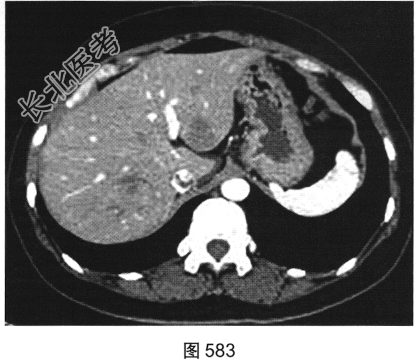

患者女性,38岁,因“间断性下腹部疼痛1周”入院。既往:否认肝炎、结核病史。查体:下腹部压痛。患者行腹部CT检查,见图582~图589。

- 多项选择题1.结合病史及影像学检查结果,可以考虑患者为以下哪些疾病( )

A、肝脏囊肿+附件囊腺瘤

B、肝脏转移瘤+附件囊腺癌

C、肝脏炎性假瘤+附件囊肿

D、肝脏炎性假瘤+输卵管积液

E、肝脏转移瘤+附件囊腺瘤

F、肝脏转移瘤+附件转移瘤

- 多项选择题4.[提示]肠镜活检病理:中分化腺癌。糖链抗原724: 46.46U/ml,癌胚抗原292.61ng/ml, 糖链抗原242:58.13U/ml, 糖链抗原199:65.78U/ml。结合影像、临床、实验室检查及镜检病理结果, 该患者术前诊断应考虑为( )

A、直肠癌,伴肝脏炎性假瘤,右侧附件转移瘤

B、直肠癌,伴肝脏转移瘤及右侧附件转移瘤

C、直肠癌,伴肝脏转移瘤,右侧附件囊腺瘤

D、直肠癌,伴肝脏转移瘤,右侧附件囊腺癌

E、直肠癌,伴肝脏转移瘤.右侧附件子宫内膜异位症

F、直肠癌,伴肝脏炎性假瘤,右侧附件囊腺瘤